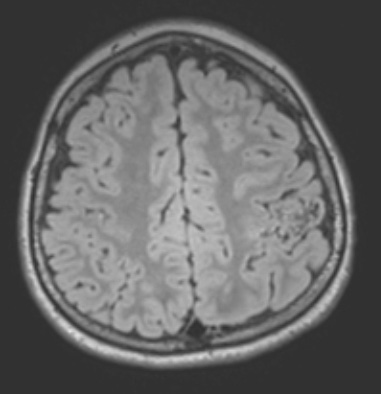

Case 34 History ---- The patient is an 8yo male with focal epilepsy in the setting of L postcentral gyrus AVM, s/p gamma knife in 2018 and most recently s/p AVM resection with clipping of feeding vessels with postoperative hemiparesis. He has not had seizures while hospitalized and remained on OXC and clobazam. CT-Angiogram post-operatively demonstrated a mixed-density subdural fluid collection, air in the resection cavity, and no filling of the prior AVM after clipping. ---- 34A1-5 MRI Studies ---- 34A1 This FLAIR MRI Scan shows a variegated hypo-/iso-intense malformation